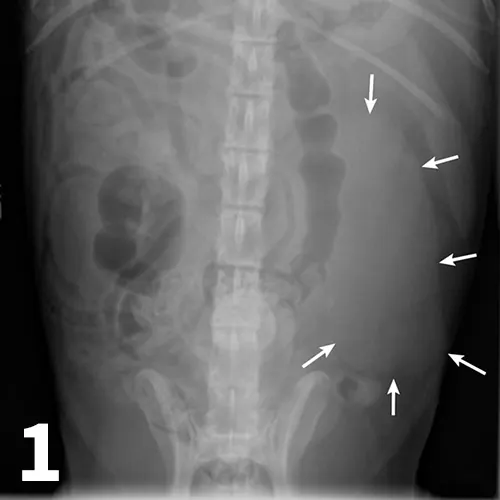

The normal urethra of dogs and cats is difficult to visualize on survey radiography and ultrasonography. Radiopaque urethroliths can be observed on survey radiographs, and therefore the entire urethra should always be included in the field of view (Figure 28). In male dogs, it is useful to pull the hindlimbs forward to assess the urethra between the pelvis and os penis (Figure 29). The prostate gland and proximal urethra, before entering the pelvic canal, can be visualized with ultrasonography, especially if there is urethral distention. In male dogs, the urethra at the proximal os penis can be evaluated with ultrasonography to assess for urethroliths, which commonly lodge in this location. Positive-contrast retrograde urethrography is the best tool for diagnosis of intraluminal, intramural, and extramural compressive urethral disorders as well urethral rupture (Figure 30).

There are 1 small and 1 large round urethral calculi (arrow) in this cat with urinary obstruction. The bladder is severely distended, and there is decreased detail caudal to the bladder. This demonstrates the importance of including the entire urethra on radiographs when urinary bladder obstruction is present or suspected.